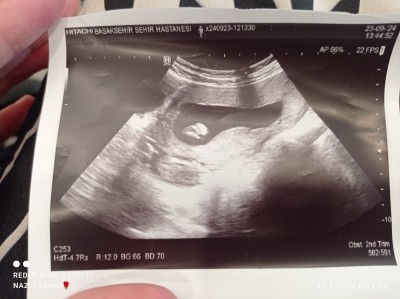

Çok merakk etim kızlar benim iki oğlum var buda kız olur inşallah

Gebelik haftası 15+6

Bacım yanlış anlama merak etmeni cok iyi anliyorum ama atığın ultrason resminde hiçbirsey beli olmuyor  cinsiyeti icin iki bacak arası gözükmesi lazım ki tahmin edelim beli  olsa  zaten doktorun  söylerdi keseye  göre dersen iki oğlumda da kesem böyle fasulye gibiydi bu kişiden kişiye farklılık gösterir ilaki hakkında hayırlısı olsun Rabb'im gönlünüze göre versin

Fotoğrafdan asla bişey belli olmuyor umarım kızınız olur

Yorumlarınız için teşekkür ederim ben de ultrason kağıdından anlamadığım için atmıştım evet doktor dedi belli değil göstermiyor ben de tahmin için atmıştım